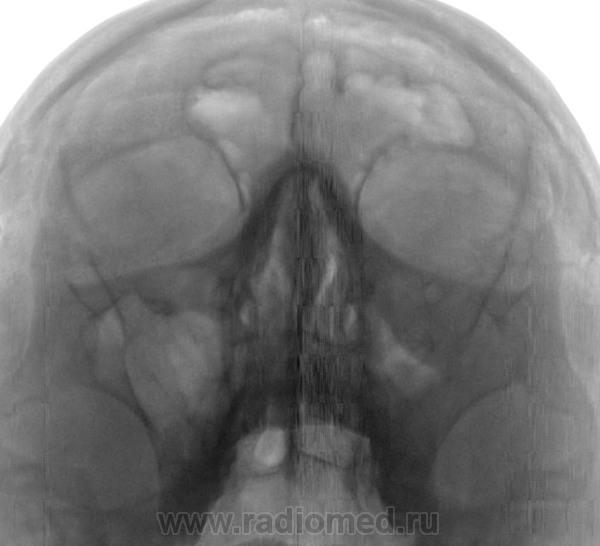

Отмечается снижение воздушности левой верхней челюстной пазухи за счет отека слизистой оболочки. Лобные пазухи и клетки решетчатого лабиринта не затемнены.

Заключение: Гайморит слева в фазе отека слизистой оболочки.

Мыли мысли по поводу фиброзной дисплазии.